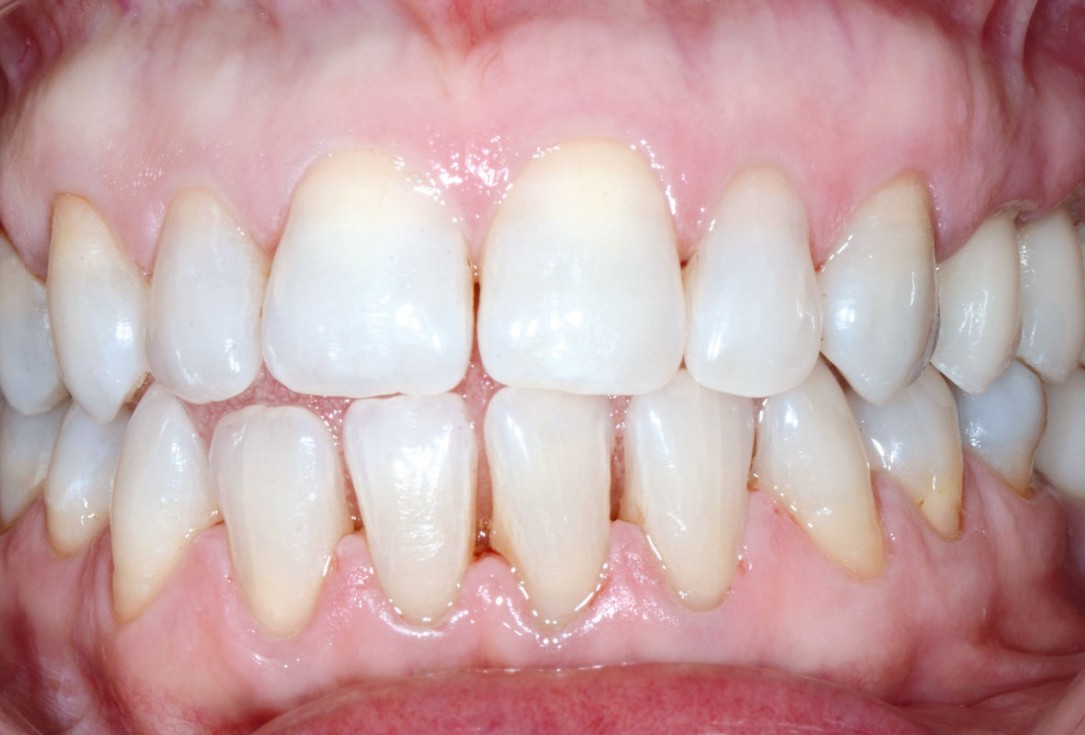

11/13 - Final prosthetic restoration one month later

Multiple socket preservation in the maxilla with collacone® max – Dr. D. Jelušić